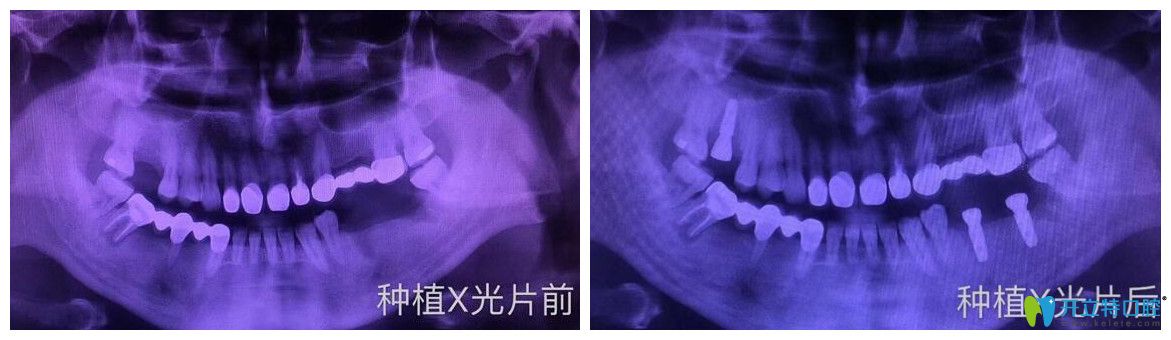

案例二:多顆牙缺失即刻種植案例

牙齒情況:種植前,牙齒意外松動(dòng)脫落,平時(shí)吃東西特別不方便

種植技術(shù):即刻種植技術(shù)

逸盛口腔口腔多顆牙缺失即刻種植案例